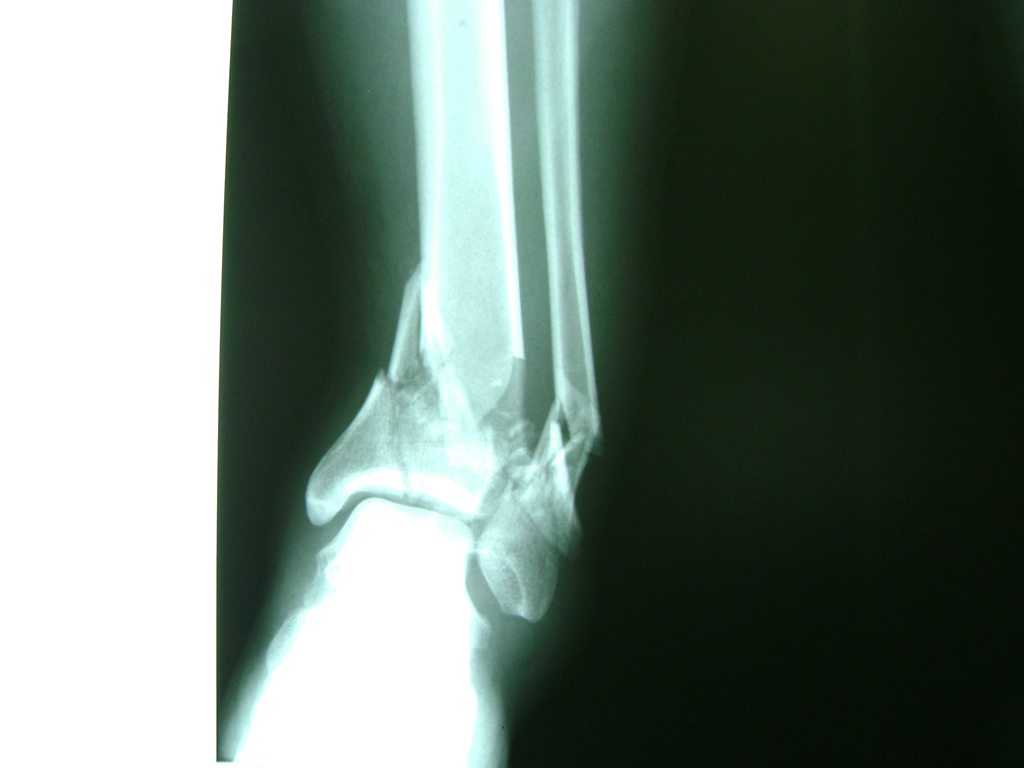

Una fractura de tobillo es la rotura de uno o más de los huesos del tobillo. Estas fracturas pueden ser:

- Parciales (el hueso está sólo parcialmente fisurado, no del todo).

- Completas (el hueso está perforado y está en 2 partes).

- Producirse en uno o ambos lados del tobillo.

- Los extremos de los huesos están desalineados entre sí (desplazados).

- La fractura se extiende hasta la articulación del tobillo (fractura intra-articular).